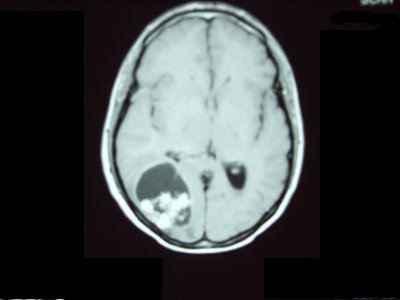

• Patología tumoral del cerebro y médula espinal.

Tumores cerebrales